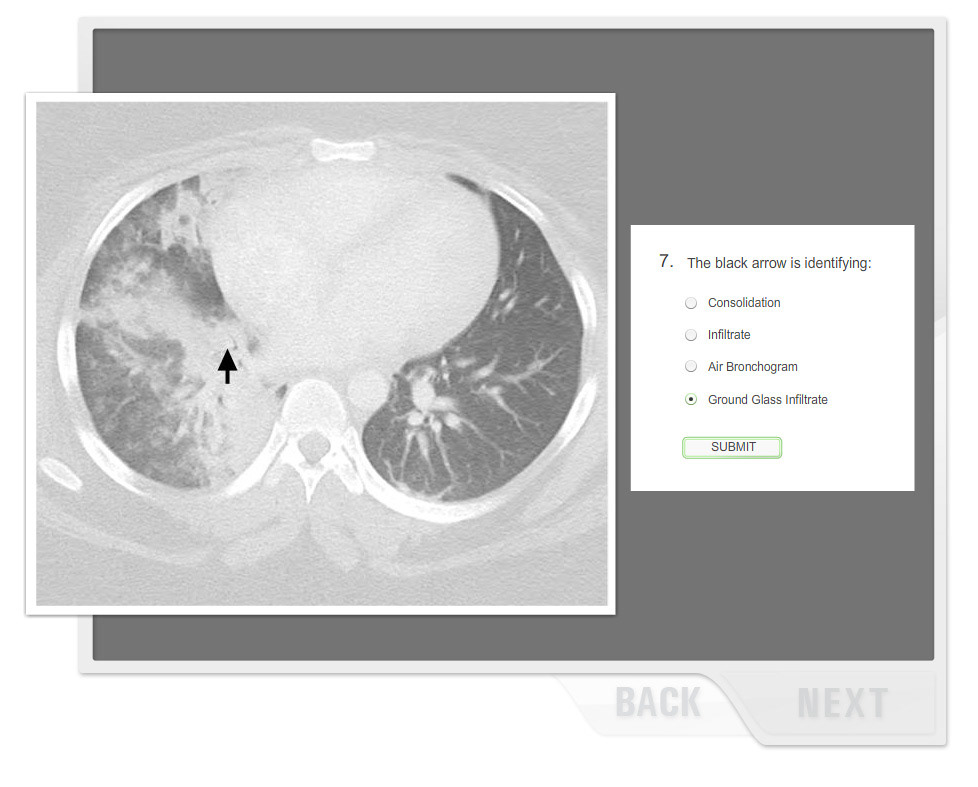

Flash Training Module

Role: Designer, Flash Developer Tools: Photoshop, Flash